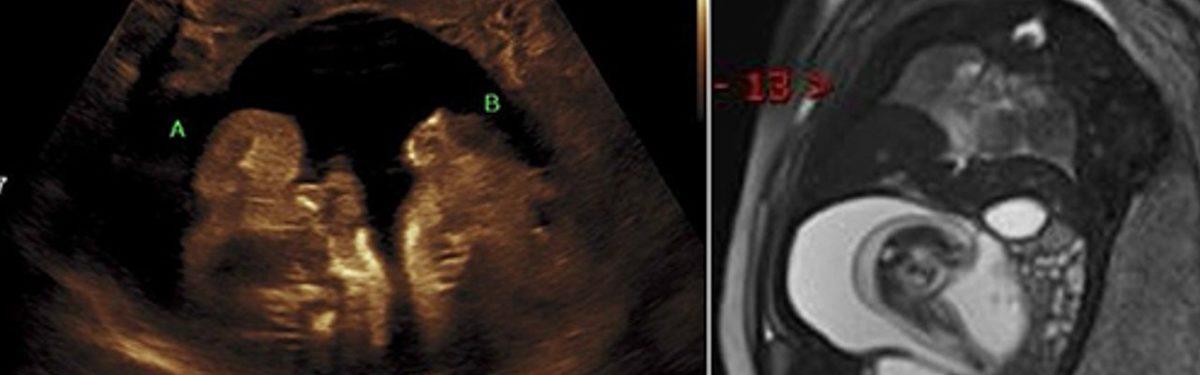

Gebelikler ortalama 38-40 hafta sürerken, bir annenin gebeliğinin 25. haftasında bir kitle tespit edildi ve bu kitleler hamilelik ilerledikçe artış gösterdi. Ultrason ve MR ile tespit edilen bu kitleler incelendiğinde, oluşumların fetüs içinde fetüs vakasıyla sonuçlanacağı anlaşıldı.

Fetüs içinde fetüs sendromu, zaman zaman hamileliğin erken dönemlerinde tespit edilemeyebilir.